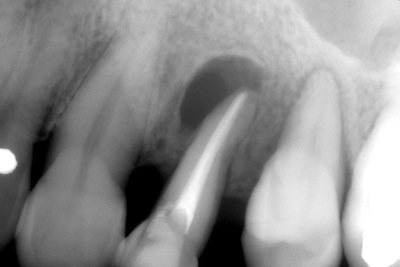

根管治療7年後 root canal treatment post 7 years

こんにちは さいたま市なると歯科院長の小林成人です

根管治療の治療例をみてみましょう

他院で抜歯してインプラントといわれた左上4番の歯

何とか残せないものかと、あわてて当院に来院されました

動揺度も大きくグラグラで、咬むと痛みがあり、エンドーペリオのリージョンがあり

確かに保存はかなり難しそうです

ダメ元で保存治療を挑戦する事にしました

根管充填時 少し影が小さくなったようななっていないような

6ヶ月後

7年後 だいぶ黒い影が小さくなってきました

ここまで症状もなく順調に経過しています

本当に抜かなくてよかったですね

今回はたまたま残せましたが、状態が悪い時は残せない場合もあります

他院で抜歯といわれた方で、何とか残せないか相談したい方は

一度ご予約ください

できるだけの事は致します